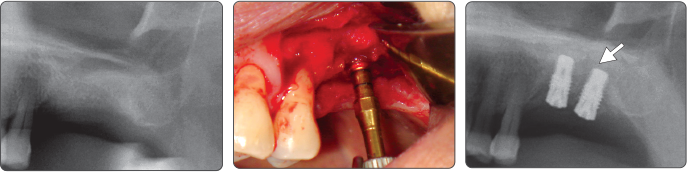

例)植入Ø4.0 Fixture

顺序-Spreader

▶ Immediate Implantation and Sinus Lift Technique with Tap Drill (Ø4.0 Fixture)